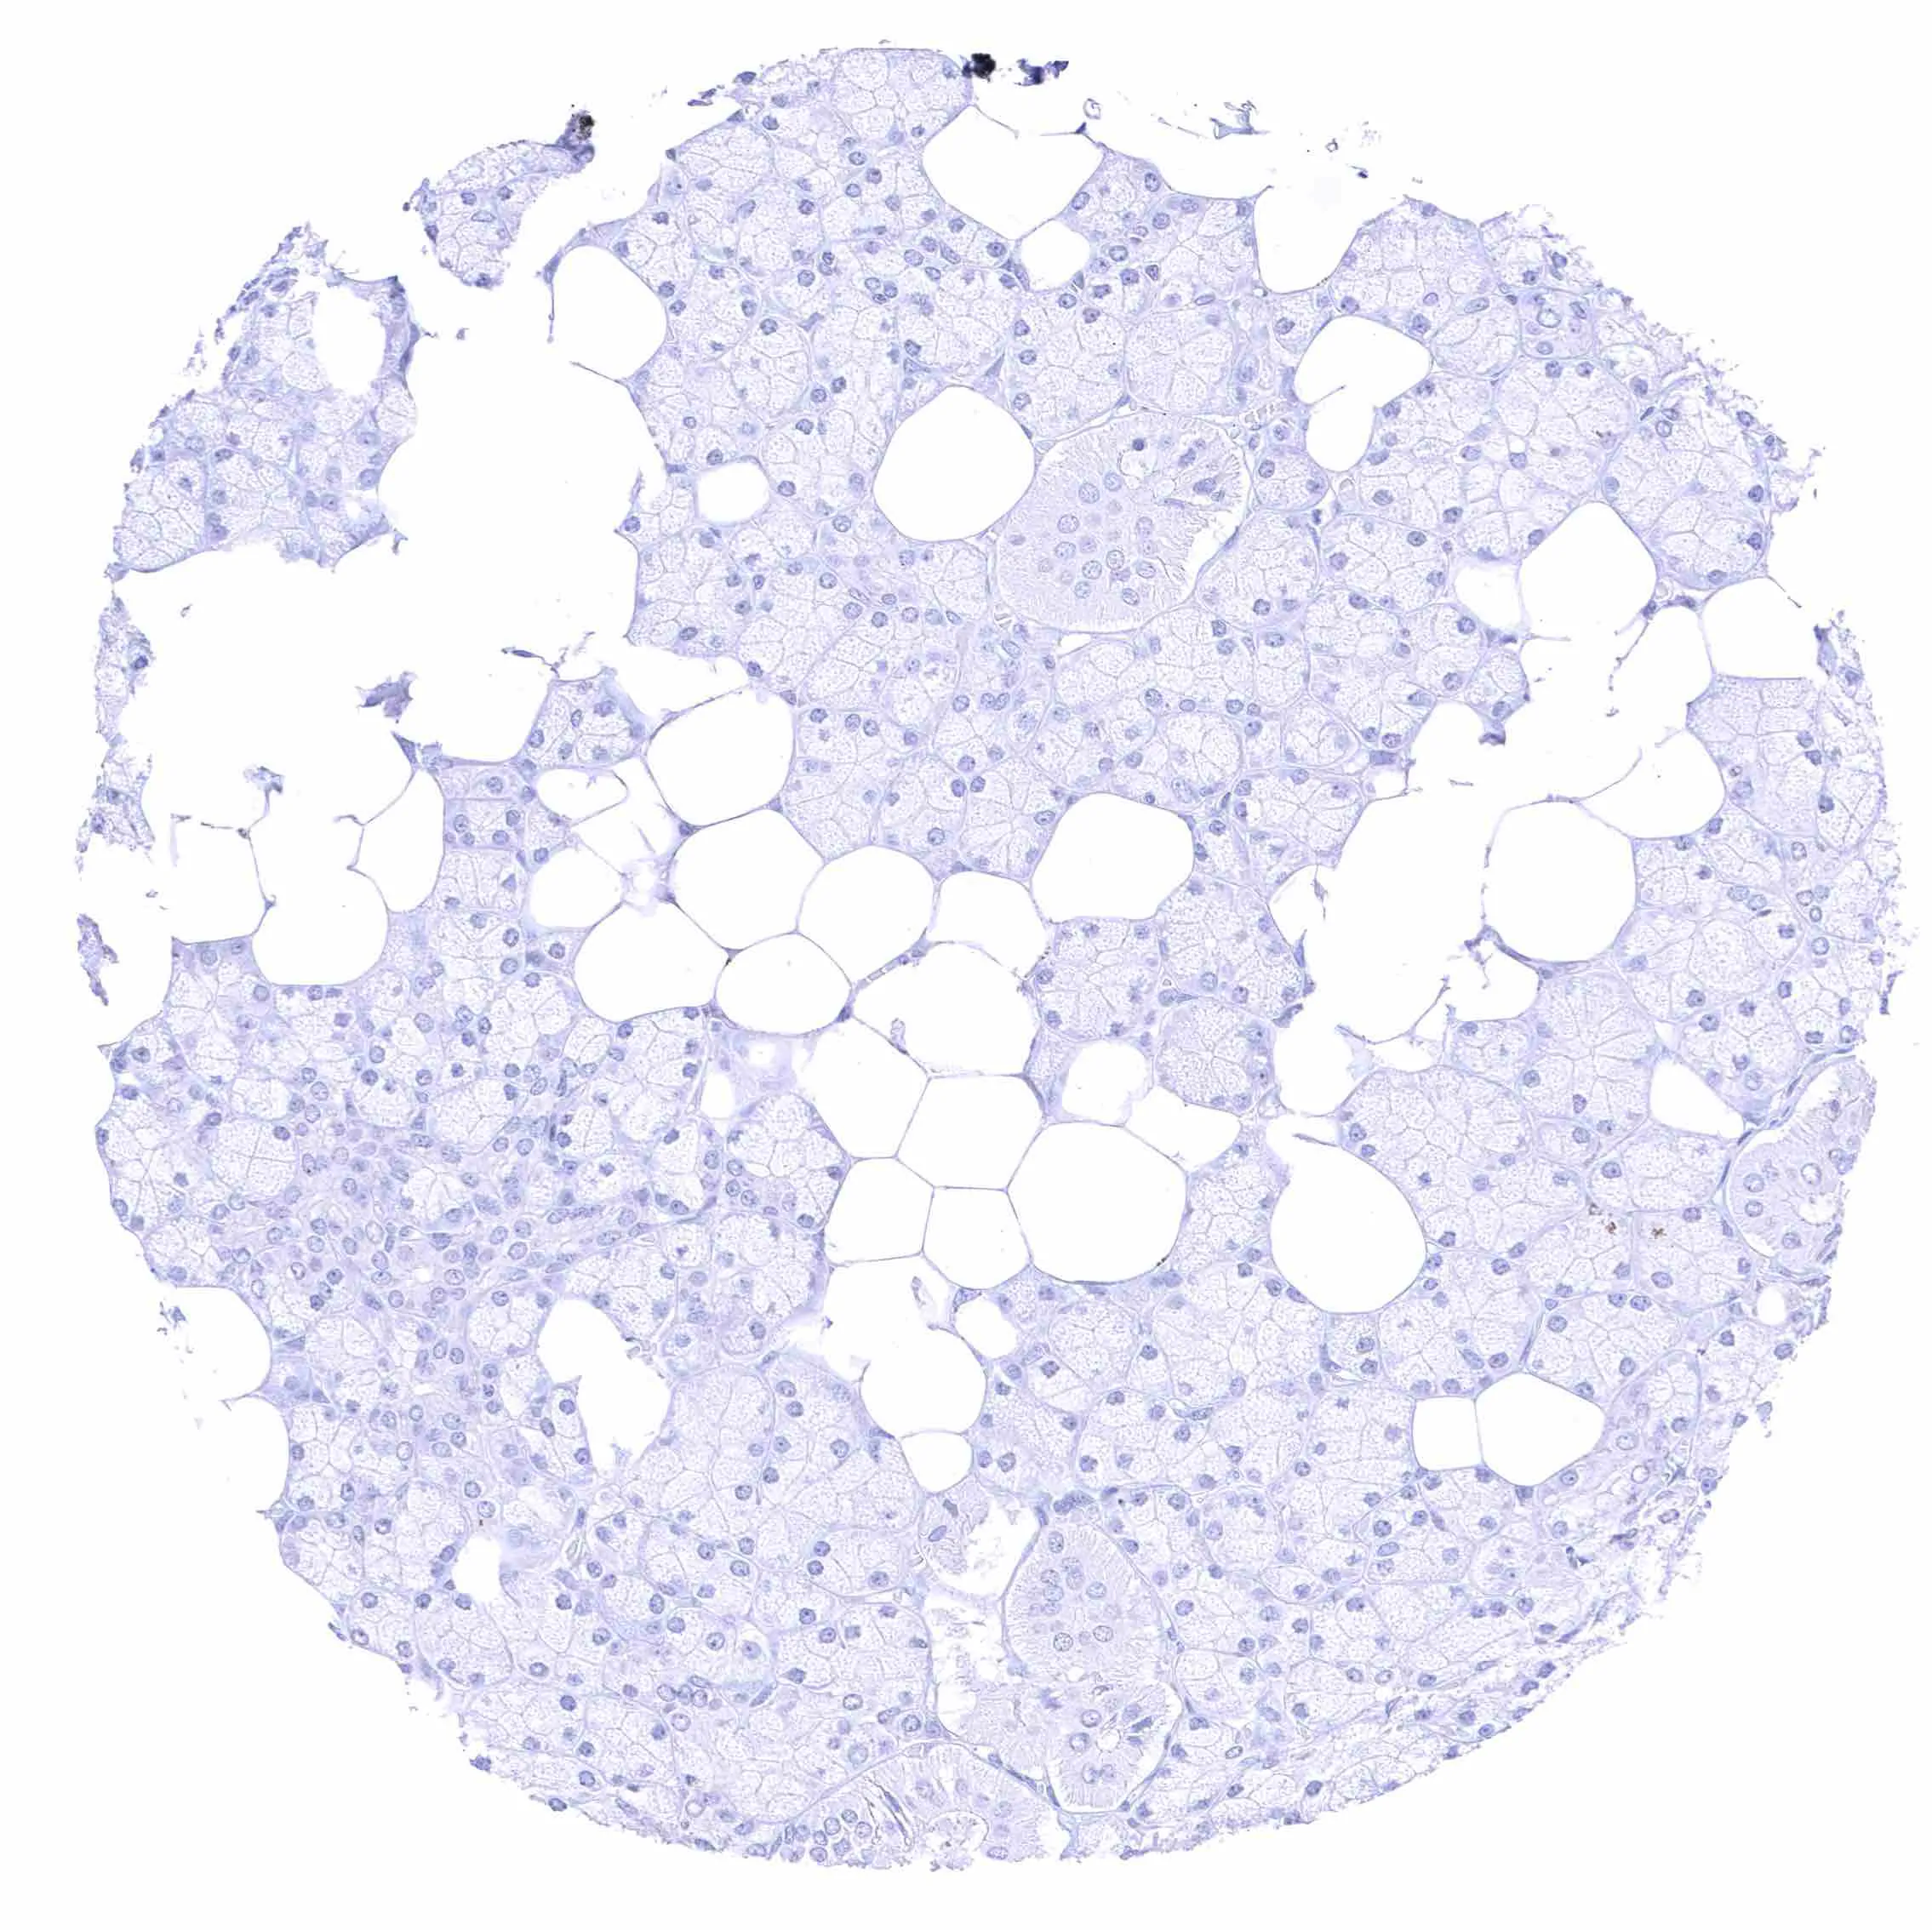

Thyroid gland